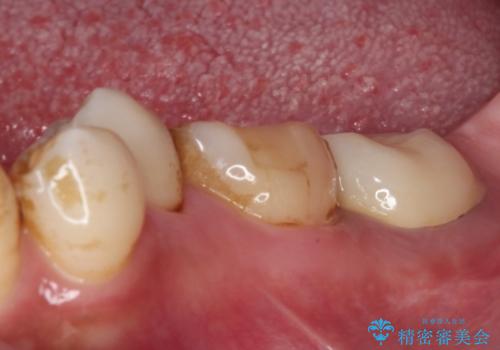

仮歯が途中外れることもなく、無事に補綴治療を行うことができました。

歯石や磨き残しなどが多いため、今後クリーニングを行っていきます。